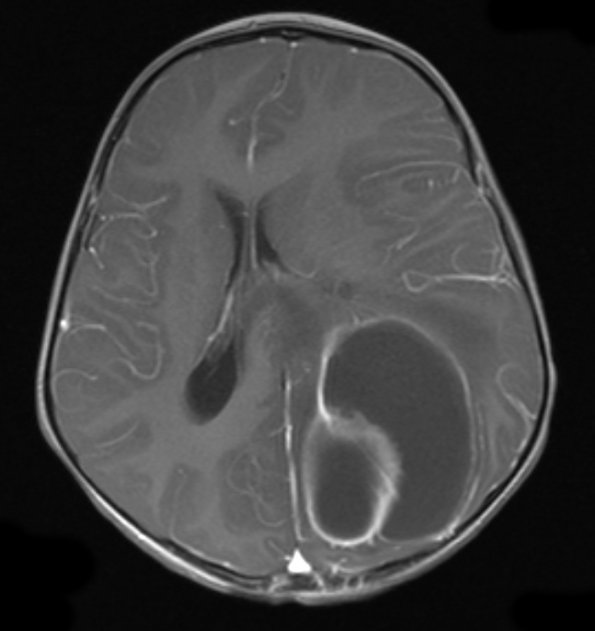

This image demonstrates the effect of administration of contrast medium on the abscess wall.